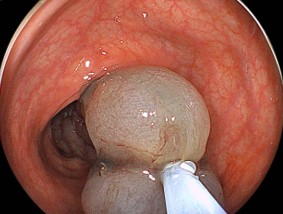

日帰り内視鏡切除の場合は、大型病変の切除後潰瘍底はclipで閉創します。

切除後の潰瘍底:切離直後の出血は、認めなかった。

最大径30mmの「早期大腸がん」で深達度は:粘膜下層;head invasion(頭部浸潤)、脈管侵襲:陰性、簇出:low、切除断端陰性であった。術後の後出血も認めなかった。